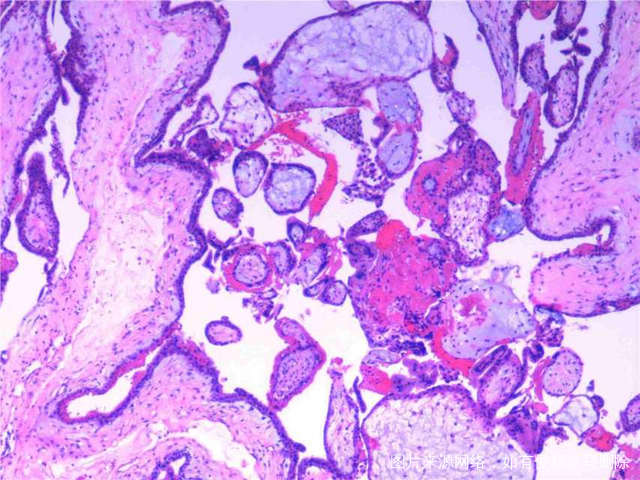

医生你好胎停了这报告正常吗